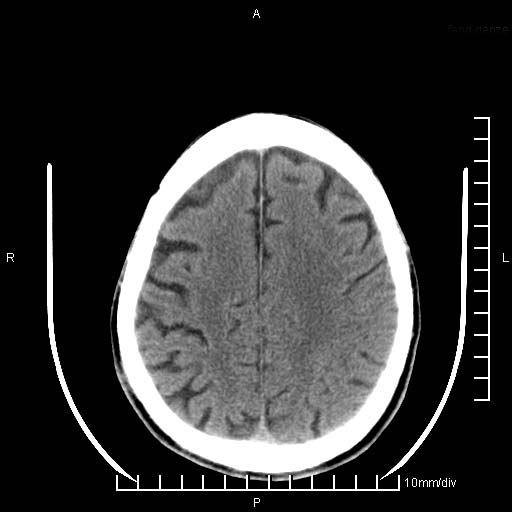

临床以双下肢浮肿,疼痛收治,无明显神经系统症状,既往无梗塞,出血病史。左颞叶见低密度灶,考虑什么?

考虑左侧颞叶脑软化灶。

无强化 无占位 软化灶吧

无强化、 无占位、局部脑沟增宽, 软化灶吧。